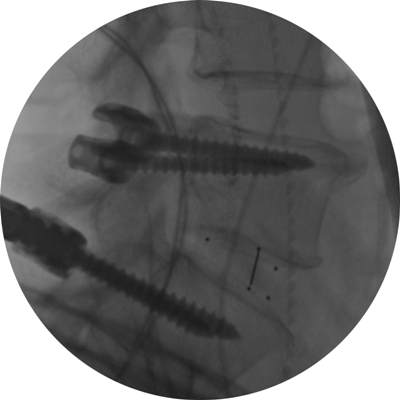

Astfel, în urma unui număr mare de investigaţii suplimentare, a fost luată decizia de a folosi un abord chirurgical numit ”fuziune intervertebrală transforaminală”. Tehnica dată este mai complicată şi mai solicitantă faţă de dotarea tehnică a blocului de operaţii şi a abilităţilor echipei chirurgicale, însă oferă un şir de avantaje pentru pacient.

Deoarece pacientul a fost operat anterior de 2 ori, utilizarea aceluiaşi coridor chirurgical tradiţional putea fi însoţită de un risc mare de leziuni a nervilor şi vaselor în canalul spinal. De aceea, a fost aleasă o cale mai puţin utilizată în practica cotidiană, dar care a fost cea mai raţională pentru pacientul dat, aşa-numitul abord paramedian transmuscular sau abordul prin spaţiul Wiltse.

Este un caz fericit pentru pacientul din Italia şi de succes pentru secţia Neurochirurgie, dar şi pentru întreaga instituţie medicală, or, astfel de intervenţii complicate au devenit posibile în Republica Moldova în urma deschiderii noului Bloc chirurgical în luna mai curent, prin intermediul căruia ţara noastră a obţinut facilităţi şi posibilităţi care au existat pînă nu demult doar în centrele medicale contemporane performante din lume. Astfel, sala de operaţii Hybrid a blocului dispune de metode de neuroimagistică intraoperatorie şi sisteme de monitoring şi neuronavigaţie, sisteme specializate de implanturi din titan şi instrumente chirurgicale, echipamente pentru disecţie osoasă. Acest complex chirurgical este completat de un departament ultradotat de anestezie şi neuroreanimare, care asigură o parcurgere perioperatorie fără complicaţii.